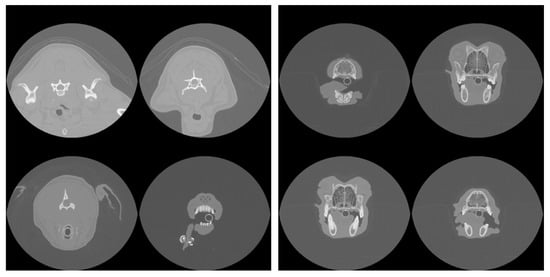

Figure 1 shows an example of the extent of cropping. Both cropped and uncropped slices were created with image dimensions of 96 × 96 pixels and 128 × 128 pixels, reduced from the original dimensions of 512 × 512 pixels of the DICOM scans. Models were trained and tested with different combinations of image resolution and cropping (see next Section 2.3).

The results of segmentation using the ResUNet++ model are shown in Table 2, and an example segmentation is shown in the bottom-right panel of Figure 1. Considering that a Dice coefficient of 1 indicates complete agreement between the predicted and ground truth segmentation masks, the findings reveal the highly accurate identification of nasal cavities by the model. Reliable segmentation is key for the success of the final phase where classification is carried out on these identified areas. Once again, the metrics show that performance degrades slightly when the model is trained and tested on the cropped scans. Figure 2 (middle panel) shows the validation loss and Dice coefficient curves for the segmentation model.

Figure 1. Example of uncropped (top-left) and cropped (top-right) scans projected onto the axial plane. Both cropped and uncropped images were tested in slice selection and segmentation, but only cropped images were used for pathology classification. The bottom-left panel shows the manually defined ground truth mask (highlighted in red) that segments the nasal cavity of the slice shown in the top-right, and the bottom-right panel shows the mask predicted by the segmentation model.